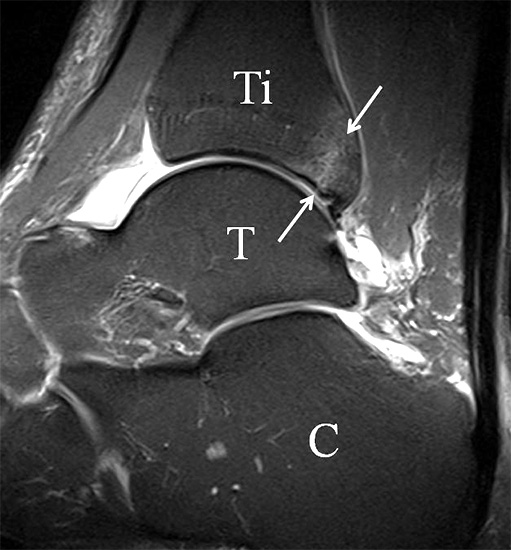

Bezogen auf die Transversalebene verläuft die Syndesmose ca. 30° schräg cranio-caudal anguliert (Abb. 15 a). Häufig lassen sich drei Hauptfaszikel differenzieren: das kürzeste superiore, das stärkste mittlere und das längste kaudale Faserbündel. Ein akzessorisches Bündel, das anteriore-inferiore, tibiofibulare Ligament (AITFL) oder auch Bassett-Ligament wird in 80-94% der Patienten nachgewiesen 8. Dies weist einen unmittelbaren Bezug zur anterolateralen Talusschulter auf (Abb. 17). In Kombination mit einer Außenbandinstabilität und konsekutivem, talarem Vorschub kann dieses zu einem Impingement an der anterolateralen Taluskante führen mit nachfolgender chondraler oder osteochondraler Läsion.

Das Ligamentum tibiofibulare posterius (hintere Syndesmose) verläuft flacher und geht nach kranial in das Ligamentum tibiofibulare interosseus und nach kaudal in das Ligamentum intermalleolare posterius über. Letzteres bildet ein artikuläres Labrum zwischen Trochlea und Talus 9.